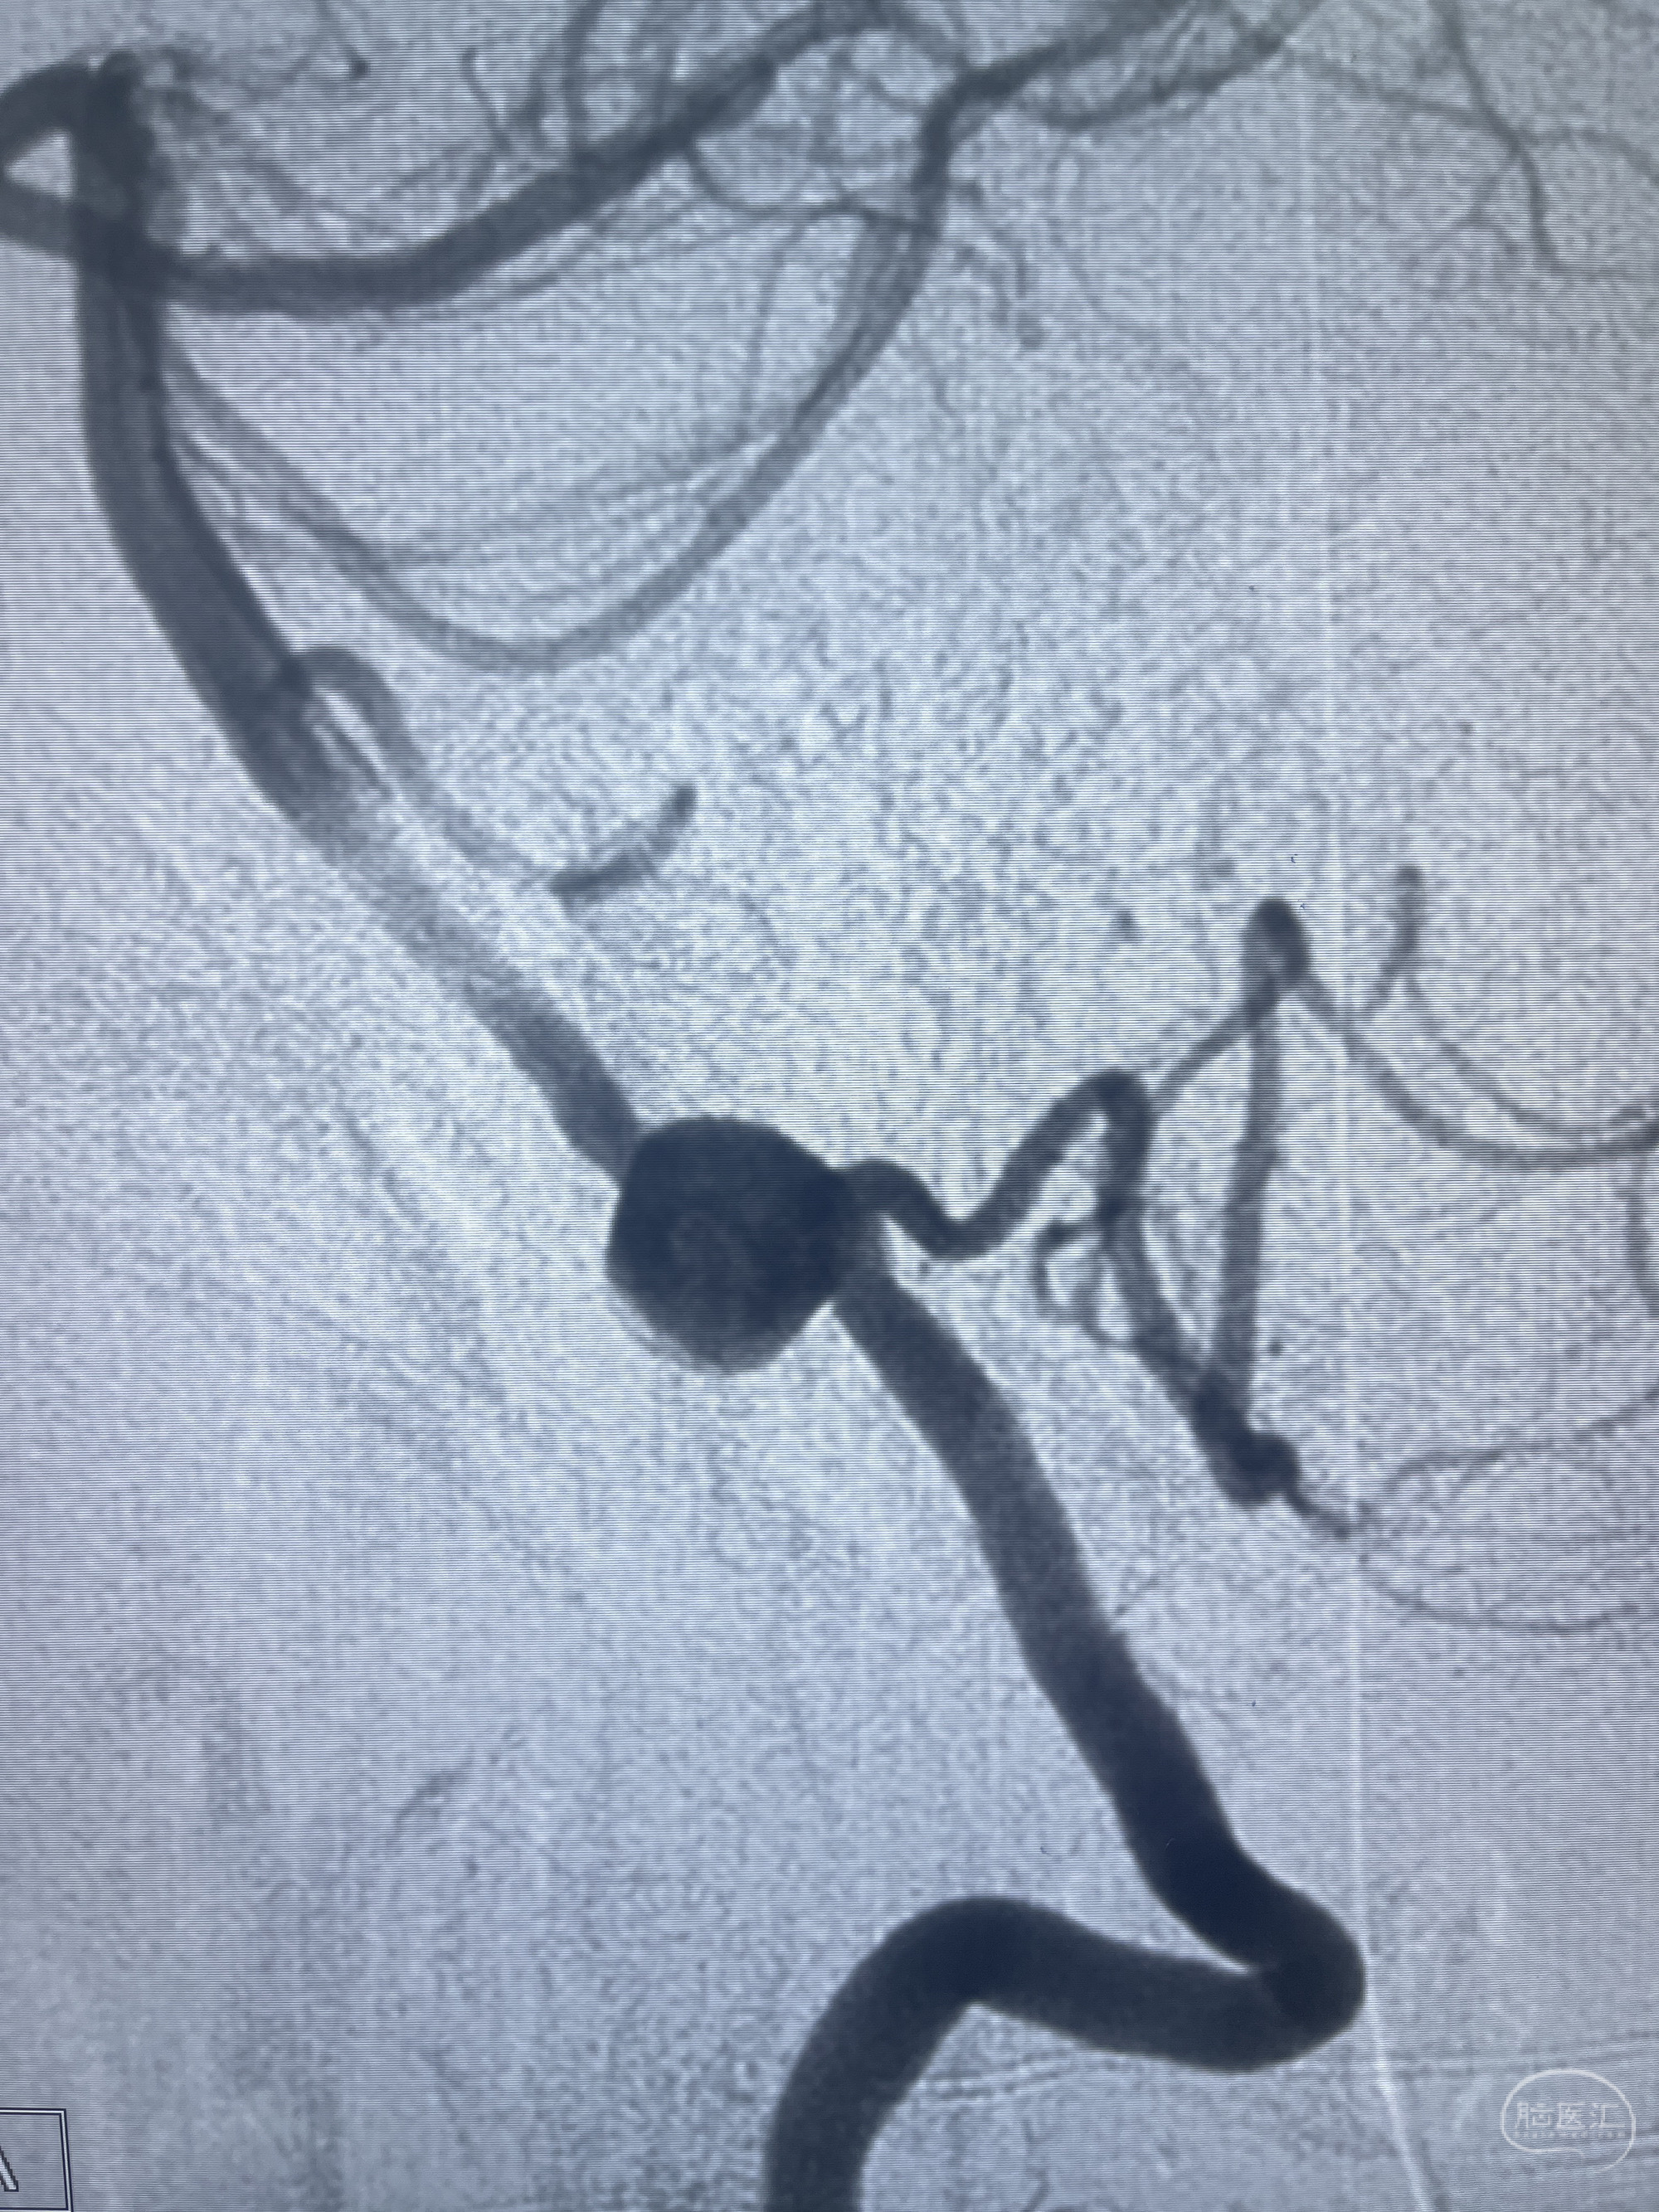

202.04.28脑血管造影:右侧大脑后动脉远段闭塞,右侧椎动脉V4段可见“囊状造影剂填充影”,大小7.64*7.65mm,可见PICA由动脉瘤发出;